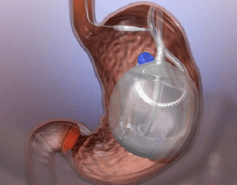

Balón Intragástrico

Se coloca un balón hecho a base de silicón, es un método seguro para bajar de peso sin necesidad de cirugía. Es un procedimiento endoscópico que se realiza de forma ambulatoria, egresando del hospital el mismo día de su colocación y el cual está indicado para pacientes con Sobrepeso u Obesidad Grado I.

El balón, en el interior del estómago genera un efecto restrictivo, disminuyendo el apetito y reduciendo la ingesta de alimento; tiene una duración de 6 meses o 1 año dependiento del tipo de balón que se coloque, con buenos resultados en la reducción de peso, logrando alcanzar el peso ideal y generando control de comorbilidades durante este lapso de tiempo. Una vez alcanzados los objetivos en cuanto a la pérdida de peso, se retira el balón mediante endoscopía de forma ambulatoria. Durante todo el lapso de tiempo en el que el paciente porta el balón, recibe vigilancia estrecha por parte del Cirujano Bariatra y cuenta con seguimiento Nutricional, asegurando que se logre una adecuada reducción de peso y se alcancen las metas establecidas en cada paciente. Los resultados pueden variar en cada paciente y pueden estar determinados por el apego de los pacientes a las indicaciones médicas.